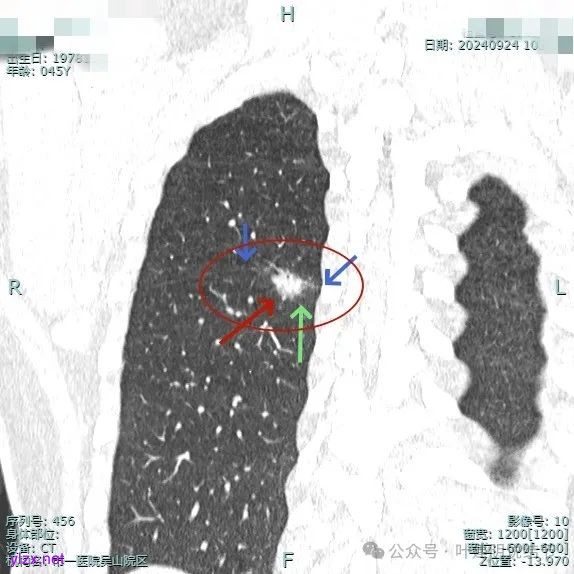

病灶3:

左下叶基底段微小结节,也是混合密度偏实性,瘤肺边界稍不清,与右侧的是类似形态的。

病灶混合密度,但瘤肺边界不够清楚,灶内也不太致密。

整个显得有点模糊,虽有血管进入,但血管说不上显著异常增粗,病灶边缘有细毛刺,贴胸膜近,但缺乏明显收缩力。

病灶显糊,轮廓较清但瘤肺边界欠清晰。

有血管进入,但病灶的感觉总好像缺乏收缩力,也聚拢性不太够。